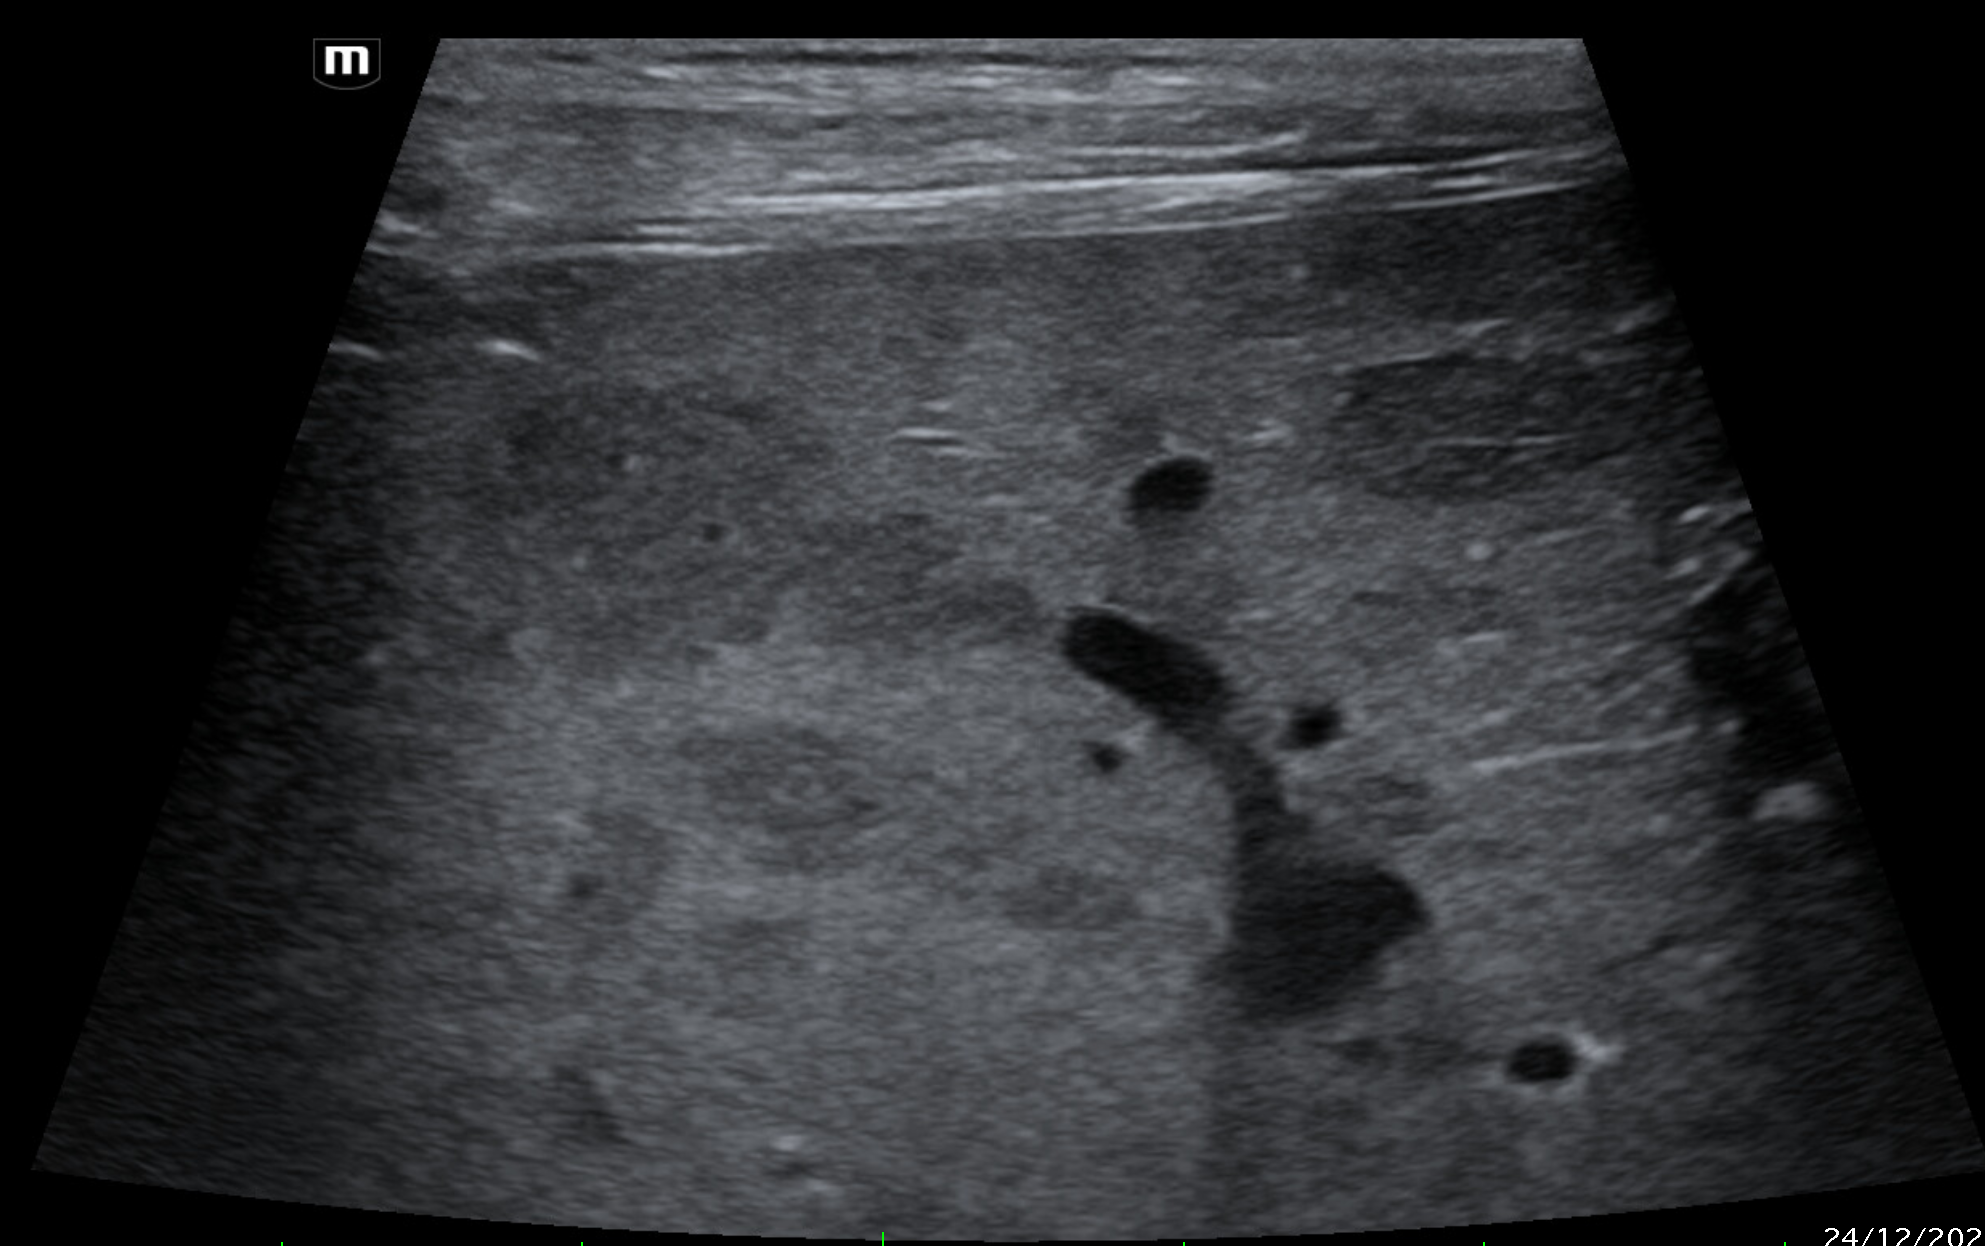

Which of these liver masses/nodules is a malignant tumor.

B-mode ultrasonography is highly sensitive for detecting focal liver lesions but is poorly specific for lesion type. Hepatic masses may appear:

• Hypoechoic, hyperechoic, or mixed echogenicity

• Well-marginated or irregular

• Solitary or multifocal

Importantly, echogenicity does not correlate reliably with malignancy. Multiple studies have demonstrated substantial overlap in the sonographic appearance of benign nodules, primary hepatic tumors, and metastatic lesions (Nyland et al., 2002; O’Brien et al., 2004)

In a large retrospective study of canine liver tumors, no consistent B-mode ultrasonographic features reliably differentiated hepatocellular carcinoma, cholangiocarcinoma, sarcoma, or metastatic lesions, aside from lesion distribution (O’Brien et al., 2004). Hepatocellular carcinomas were more likely to be solitary, whereas sarcomas and metastases were more often multifocal, but significant overlap existed.

Doppler Ultrasonography

Color and power Doppler ultrasound allow assessment of vascular architecture and blood flow within hepatic lesions. Malignant tumors may demonstrate

• Internal or peripheral neovascularization

• Tortuous or irregular vessel

However, Doppler findings overlap considerably between benign and malignant lesions, and vascularity alone cannot be used to determine tumor type (d’Anjou & Penninck, 2015). Doppler imaging is most useful for: